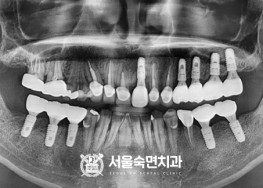

임플란트-치료-전후사진